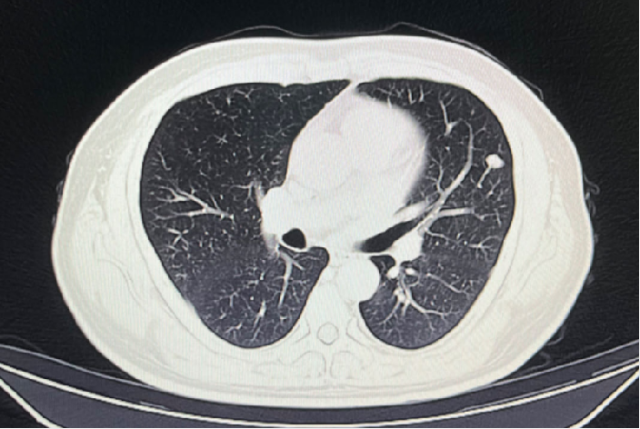

影像学检查

2024-02-28: